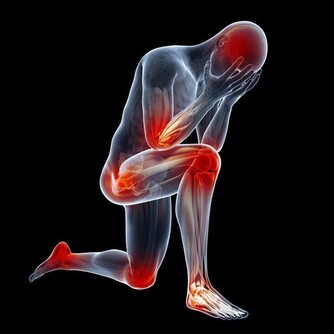

膝蓋的天敵

1.年齡

早在青少年時期,關節軟骨就開始退化,

骨關節炎開始趁機蠢蠢欲動。

隨著年齡增長,血液循環及肌肉變弱,

關節部位因潤滑液分泌減少而變干,

軟組織的彈性減弱,更易受到拉傷的威脅,

同時軟骨變得易砰易剝落;

半月板也開始退化並缺乏重建的能力,

這個問題因體重增加而惡化。